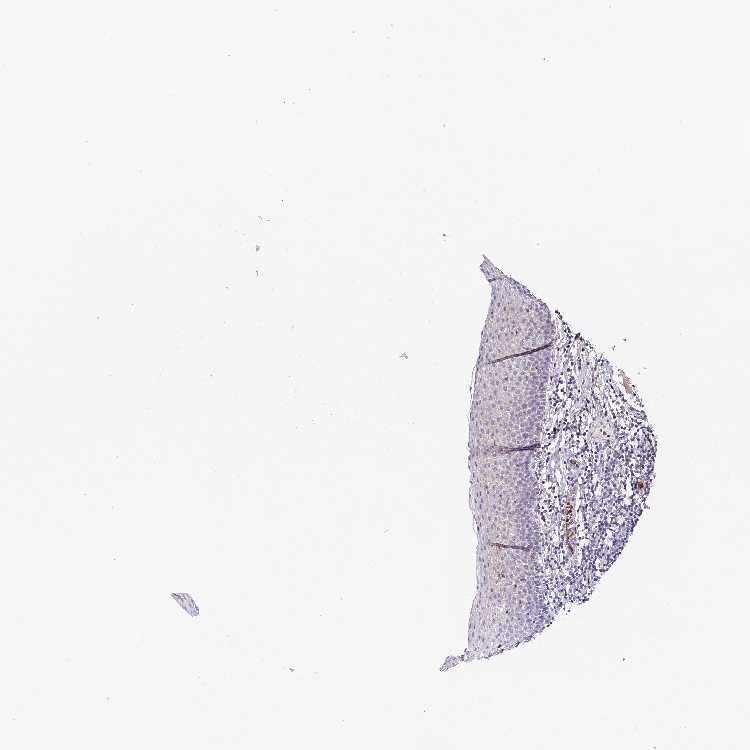

TISSUE PRIMARY DATA ORAL MUCOSA Show tissue menu

ORAL MUCOSA - Antibody stainingi

Antibody staining in the annotated cell types in the current human tissue is reported as not detected, low, medium, or high, based on conventional immunohistochemistry profiling in selected tissues. This score is based on the combination of the staining intensity and fraction of stained cells.

Each image is clickable and will lead to virtual microscopy that enables deeper exploration of all samples and also displays staining intensity scores, fraction scores and subcellular localization as well as patient and tissue information for each sample.

Antibody HPA042439

Squamous epithelial cells Not detected